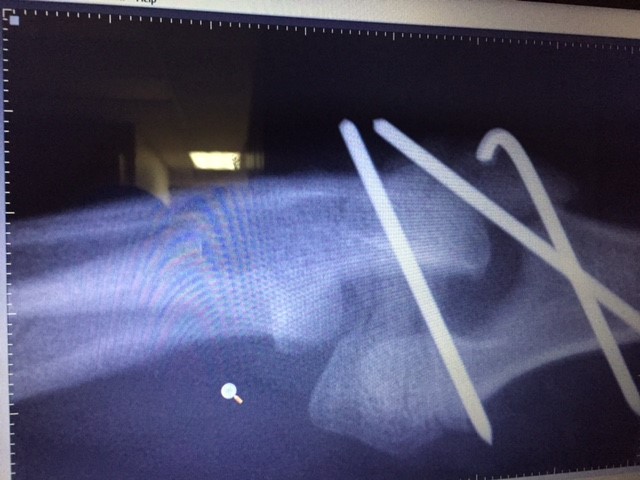

Hit by Car - 2 year old Labrador Retriever, External Fixator to repair transverse tibia/fibula break